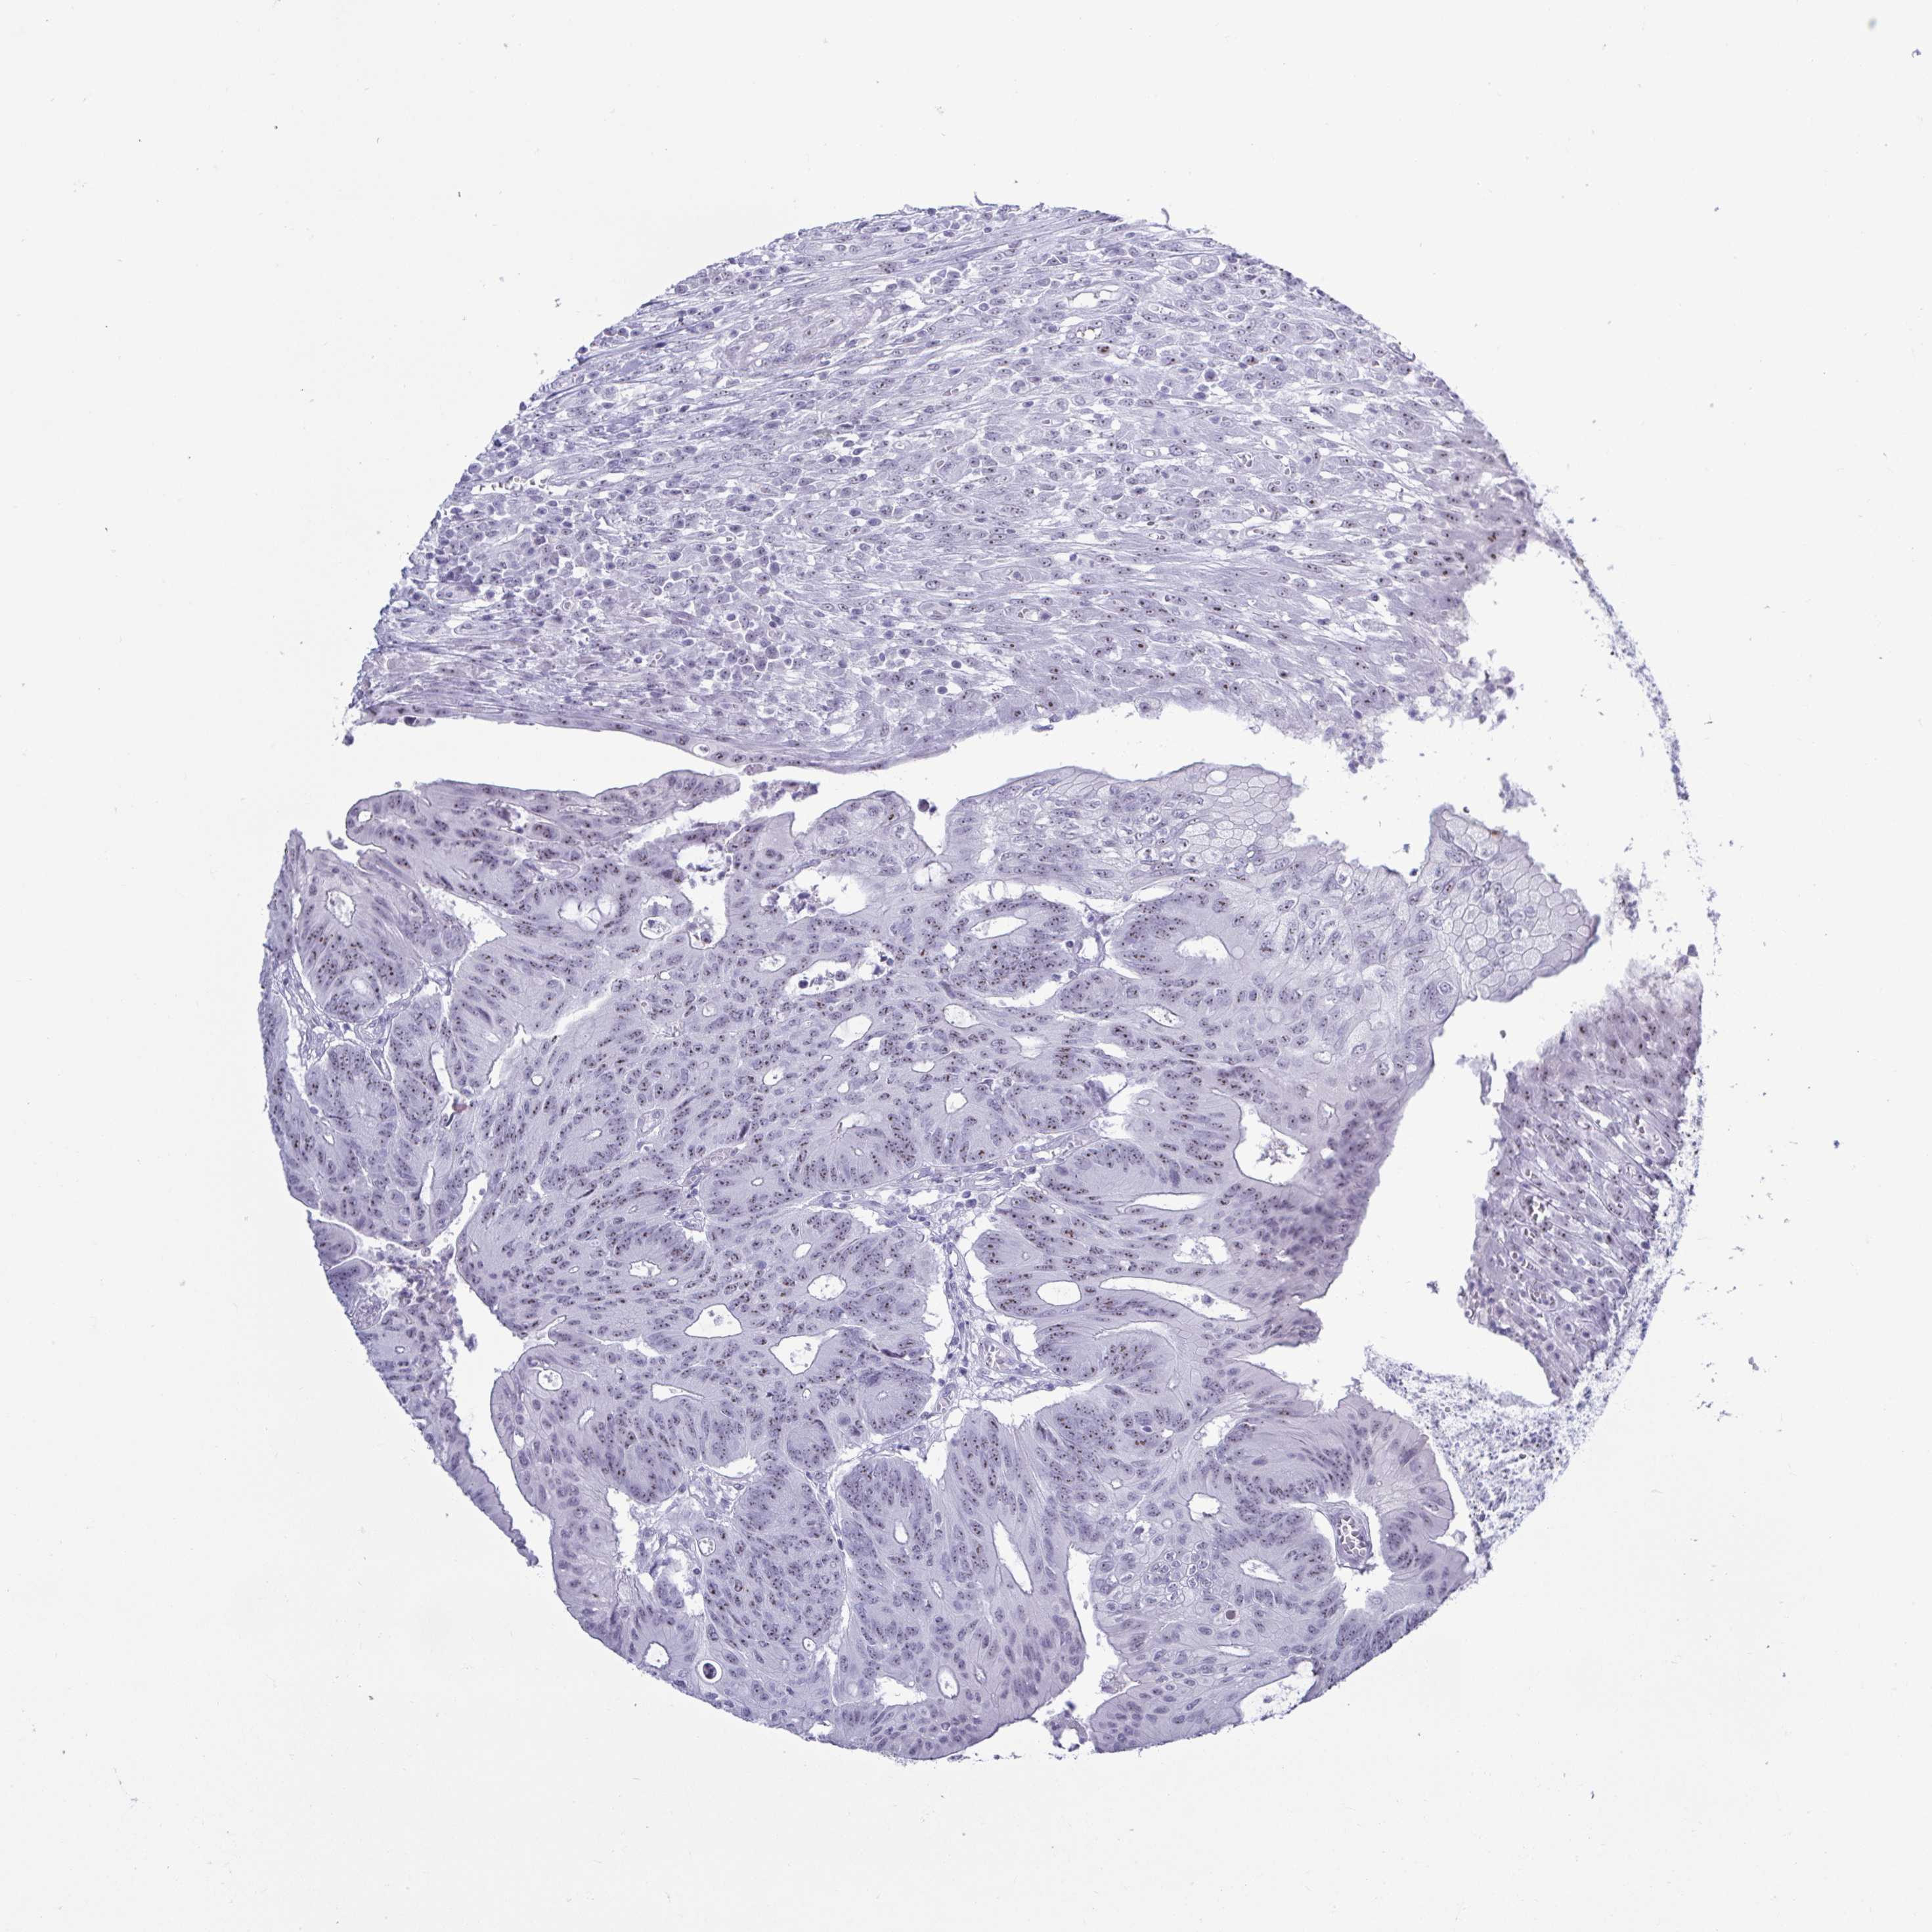

CANCER COLORECTAL CANCER Show tissue menu

Colorectal cancer

Human cancer

Colon adenocarcinoma